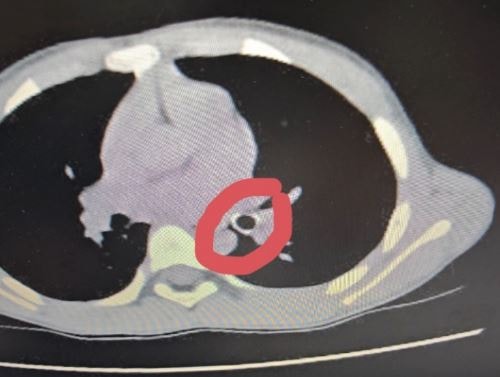

Hình ảnh dị vật trên phim X-quang. Ảnh: BVCC.

Qua thăm khám lâm sàng, các bác sĩ nghi ngờ trẻ bị hóc dị vật đường hô hấp. Sau khi chụp CT ngực, kết quả ghi nhận dị vật hình ống, bề dày thành khoảng 1,8mm, chiều dài khoảng 18mm, nằm tại phế quản thùy dưới trái, gây cản trở thông khí.

Dị vật là đầu ngòi bút, bề dày thành khoảng 1,8mm, chiều dài khoảng 18mm.